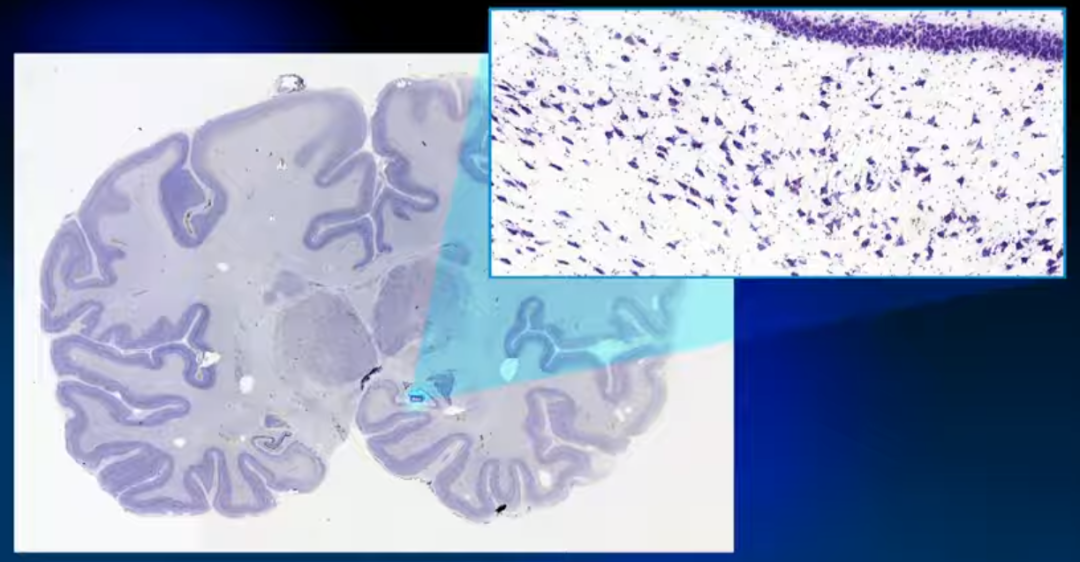

随后进行染色和数字化,获取全脑的组织学信息

专家根据被染色的细胞聚集的情况找到组织的边界,作为随后定位和分割的解剖参考